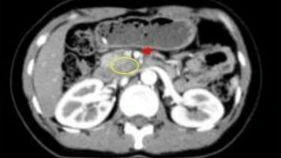

Ung thư tụy là một bệnh lý có tiên lượng xấu và trường hợp này càng trở nên khó khăn khi khối u đã lan rộng ra khắp tuyến tụy. Người bệnh được phát hiện tình trạng bệnh trong một lần kiểm tra sức khỏe định kỳ. Khối u được chẩn đoán có kích thước lớn, tăng sinh mạch toàn bộ tụy, huyết khối tĩnh mạch lách, đồng thời xâm lấn lách và đại tràng góc lách.

Đây là một thủ thuật điện quang can thiệp nhằm hạn chế các mạch máu tăng sinh nuôi khối u, chuyển một khối u giàu mạch máu thành một khối u an toàn hơn để thực hiện phẫu thuật.